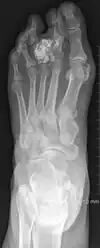

| Non-cancerous | Subungal exostosis[2] | ![]() |

| Bizarre parosteal osteochondromatous proliferation[2] | ![]() | |